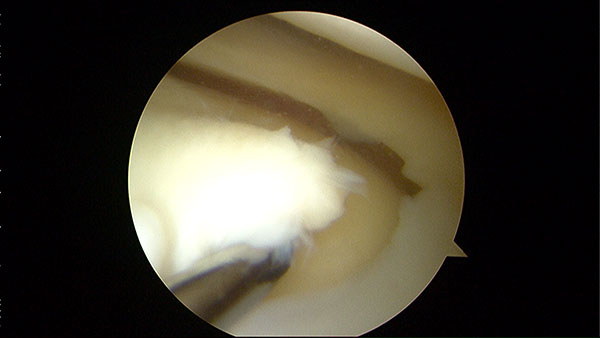

Chondral Defect

-

Chondral Fragment

Chondral Tibial Flap And Microfracture